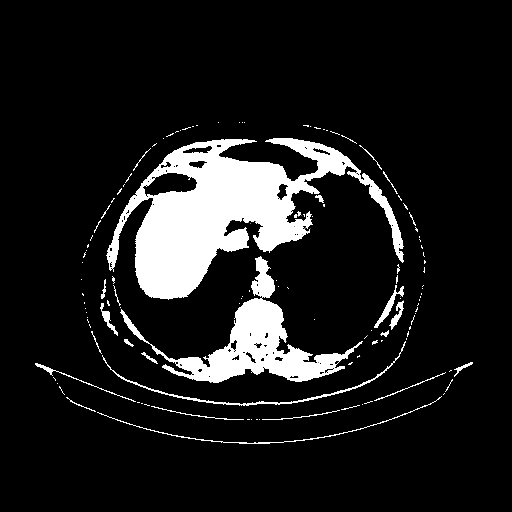

Original NATIVE CT scan (input)

Full window (WL 1023.5, WW 4095 β†’ Low βˆ’1024, High +3071)

Actual HU range: [-1024.0, 3071.0]